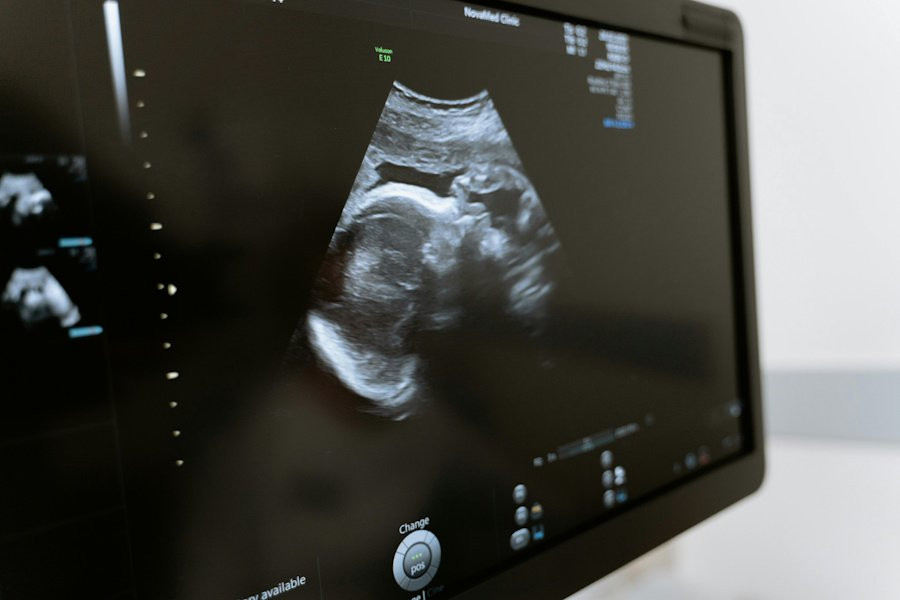

Суррогатное материнство связано с повышенным риском осложнений беременности

Ученые из McGill University (Канада) провели масштабное исследование, которое показало, что суррогатные матери сталкиваются со значительно более высоким риском серьезных осложнений во время беременности. Результаты работы были опубликованы в медицинском журнале Annals of Internal Medicine.

Эксперты изучили данные о 863 017 одноплодных родах, из которых 806 приходилось на гестационных носителей — так называют женщин, вынашивающих детей для других людей. Результаты исследования оказались тревожными: вероятность тяжелых материнских заболеваний среди суррогатных матерей составила 7,8%. Это более чем в три раза выше, чем у женщин, зачавших ребенка самостоятельно, и почти в два раза выше по сравнению с женщинами, прошедшими процедуру экстракорпорального оплодотворения (ЭКО).